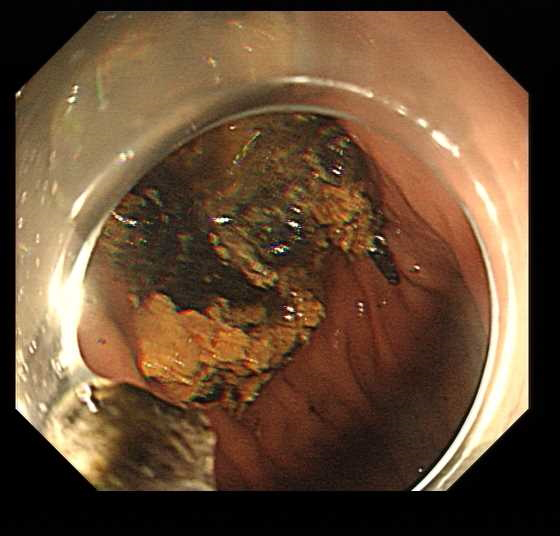

面对金大妈胃中这颗质地坚硬的“金丹”,章医生联合消化内镜团队制定了一套周密的治疗方案。他们使用了多把圈套器,小心翼翼地先将结石捣碎成小块,再逐一取出。

“胃结石的治疗方法多样,主要取决于结石的大小和质地。”章医生介绍,“较小的结石可以通过饮用可乐等酸性液体软化溶解,但像金大妈这种较大且坚硬的结石,往往需要内镜下碎石或外科手术取石。”

整个内镜下治疗过程持续了一个多小时,当最后一块碎石被取出时,医护人员都松了一口气。金大妈胃里的“修真金丹”终于被成功摘除。